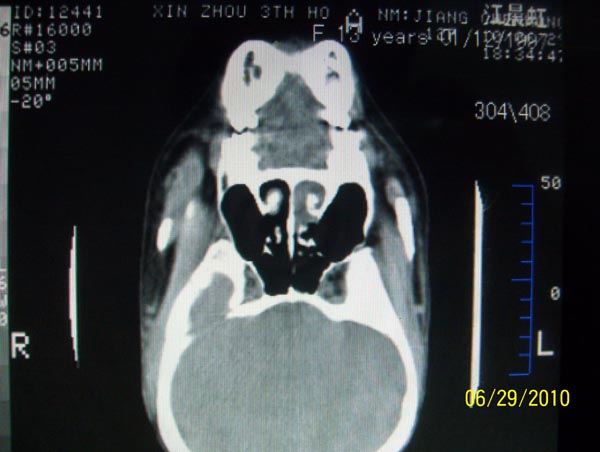

以下是引用随光逐影在2010-6-29 22:28:00的发言:[br]1)右侧下鼻甲肥大(或息肉样变)。2)鼻咽腺样体肥大。

以下是引用随光逐影在2010-6-29 22:28:00的发言:[br]1)右侧下鼻甲肥大(或息肉样变)。2)鼻咽腺样体肥大。

以下是引用随光逐影在2010-6-29 22:28:00的发言:[br]1)右侧下鼻甲肥大(或息肉样变)。2)鼻咽腺样体肥大。

以下是引用拾荒者在2010-6-30 19:22:00的发言:[br]右侧下鼻甲粘膜肥厚,鼻腔阻塞,鼻旁窦窦腔清晰,支持考虑慢性鼻炎。